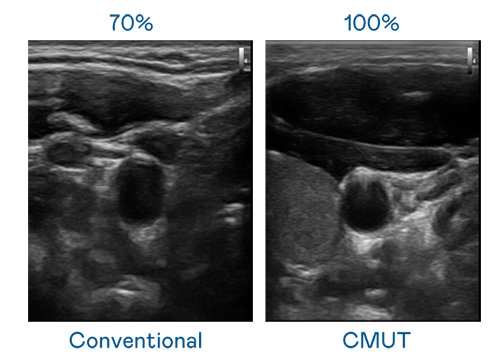

CMUT 技术是一种用电容式微机电元件来产生超音波讯号的技术。与传统 PZT 压电式技术相比,CMUT 频宽增加 30%,更宽频的超音波讯号让影像解析度大幅提升,是实现高影像品质医疗超音波扫描、促进精准医疗发展的关键技术。

大频宽带来超清晰影像

超音波影像的解析度高低,首先取决于探头能发出的讯号频宽。永利集团304 CMUT 可提供高清晰的超音波讯号,提供高频宽、高灵敏度、影像纹理细节更高的超音波影像,协助医护人员缩短影像判读时间及利用精准的医疗影像进行诊断。